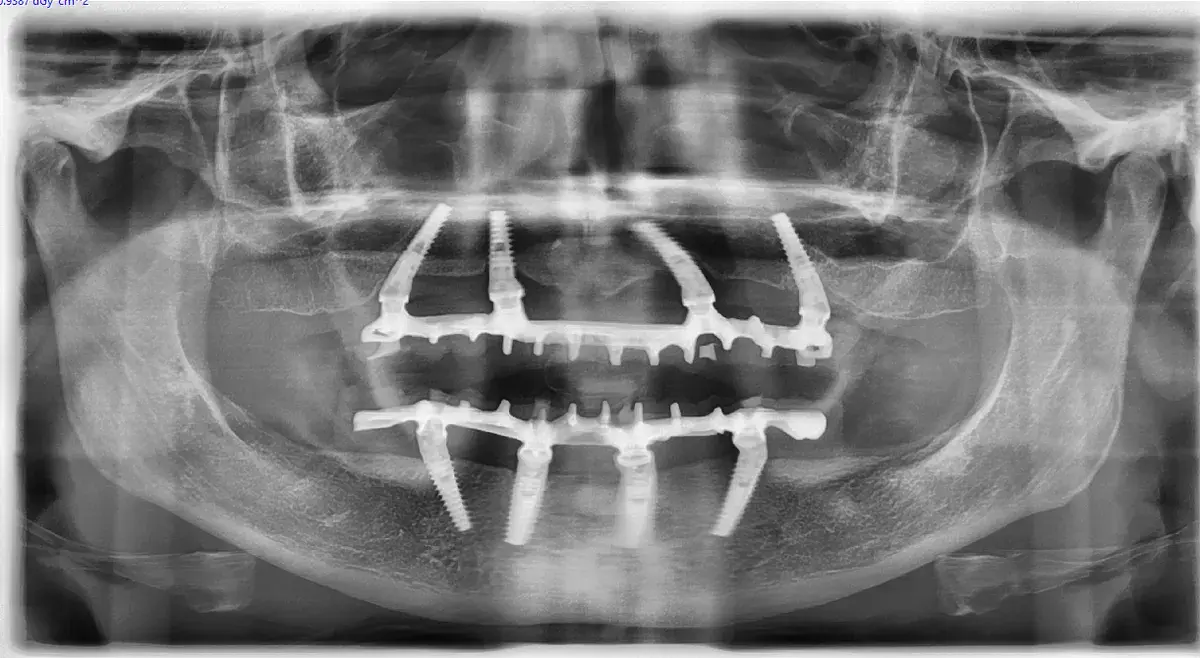

Caso clinico di carico immediato su rialzo crestale del seno mascellare con espansori. Espansione apicale, stabilità >50 Ncm, provvisorio immediato e co...

Meta-analisi su 1.400 impianti conferma l'efficacia dell'espansione osteo-mucosa: 98.1% di sopravvivenza. Scopri le novità e le mie considerazioni clini...

Scopri come funziona l'implantologia a carico immediato, quando è possibile applicarla e quali vantaggi offre. Guida del Dr. Ernesto Bruschi.